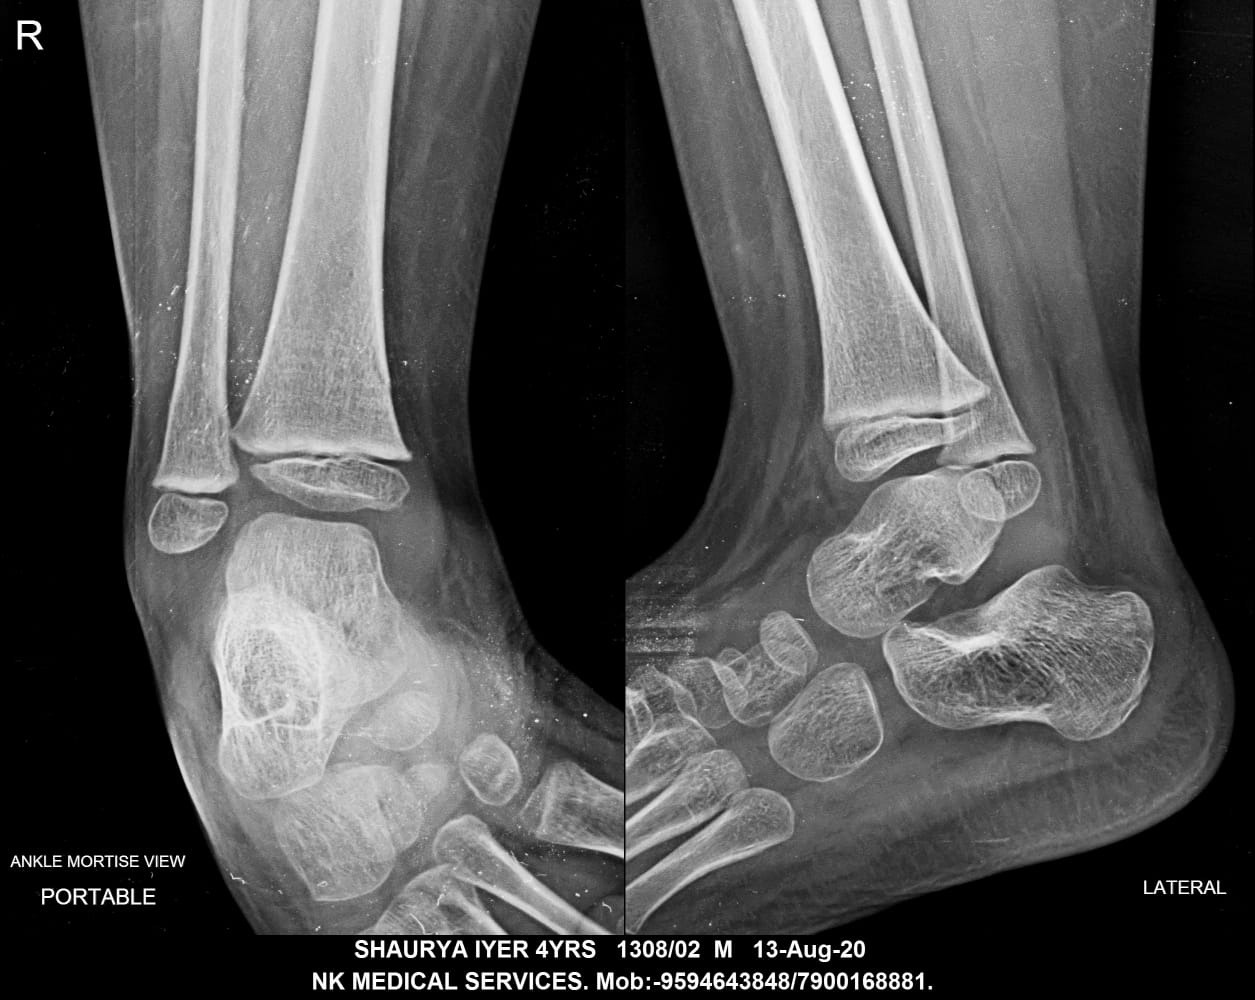

Getwell Urgent Care of Southaven uses digital X-ray technology, which uses less radiation, provides fast turnaround of images, and gives us the ability to manipulate images for more accurate readings. We follow the highest safety standards, with certified equipment and licensed radiology technologists to ensure an excellent image the first time and minimal exposure to radiation. We use digital X-ray to diagnose broken bones, certain lung conditions (e.g., pneumonia), and certain abdominal conditions.